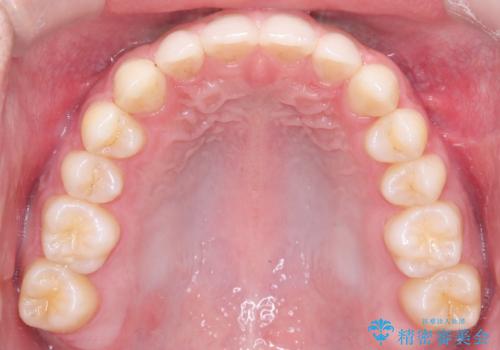

- 主訴:上の歯列の空隙を閉じたい

上顎前歯部に空隙が目立ちました。ワイヤー矯正、インビザライン(マウスピース矯正)どちらの方法でも適用症例と説明し、ワイヤー矯正治療(審美装置)を希望されました。

上顎歯列の空隙を閉じるのと一緒に、ディープバイト気味の被蓋も下顎前歯の圧下を行い改善しました。